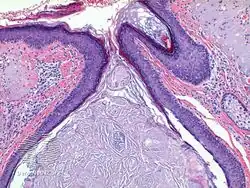

Chronic exposure to ultraviolet light can result in skin thickening as well as elastic destruction of the skin. At least in one instance, the occupational exposure to the UVA light of the sun (UVB is blocked by many car windows) resulted in skin destruction on one side of the face.[2] Microscopically, Favre–Racouchot displays multiple dilated follicular cysts/milia and open comedones with severe solar elastosis in the background dermis.

Favre–Racouchot syndrome-pathology